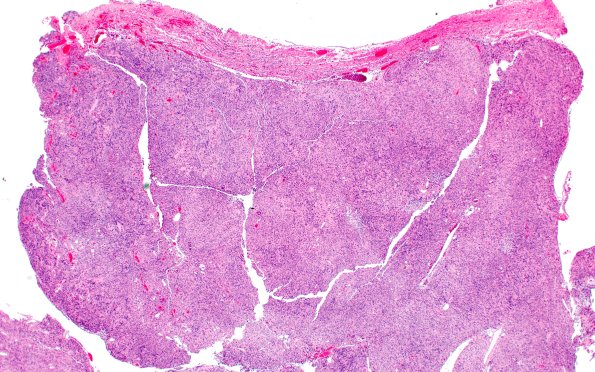

Washington University Experience | NEOPLASMS - CRANIAL AND PARASPINAL NERVEs | Schwannoma | 30B1 Schwannoma (Case 30) H&E 2X B

30B1,2 H&E-stained sections show a benign spindle cell neoplasm with hypercellular areas containing numerous Verocay bodies, and hypocellular areas with variable numbers of foamy macrophages. The tumor abuts but does not invade the adjacent nerve with Scarpa’s ganglion, the ganglion of the vestibular branch of the vestibulocochlear nerve. Tumor nuclei are short spindled to wavy and demonstrate focal degenerative atypia ("ancient" change). Mitotic activity is rare. There are scattered hyalinized thickening of blood vessels and foci of chronic lymphocytic infiltrate. (H&E)